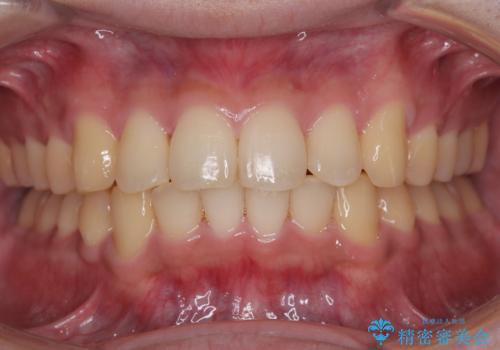

前歯と奥歯のガタガタを矯正で改善

担当医 河口智英